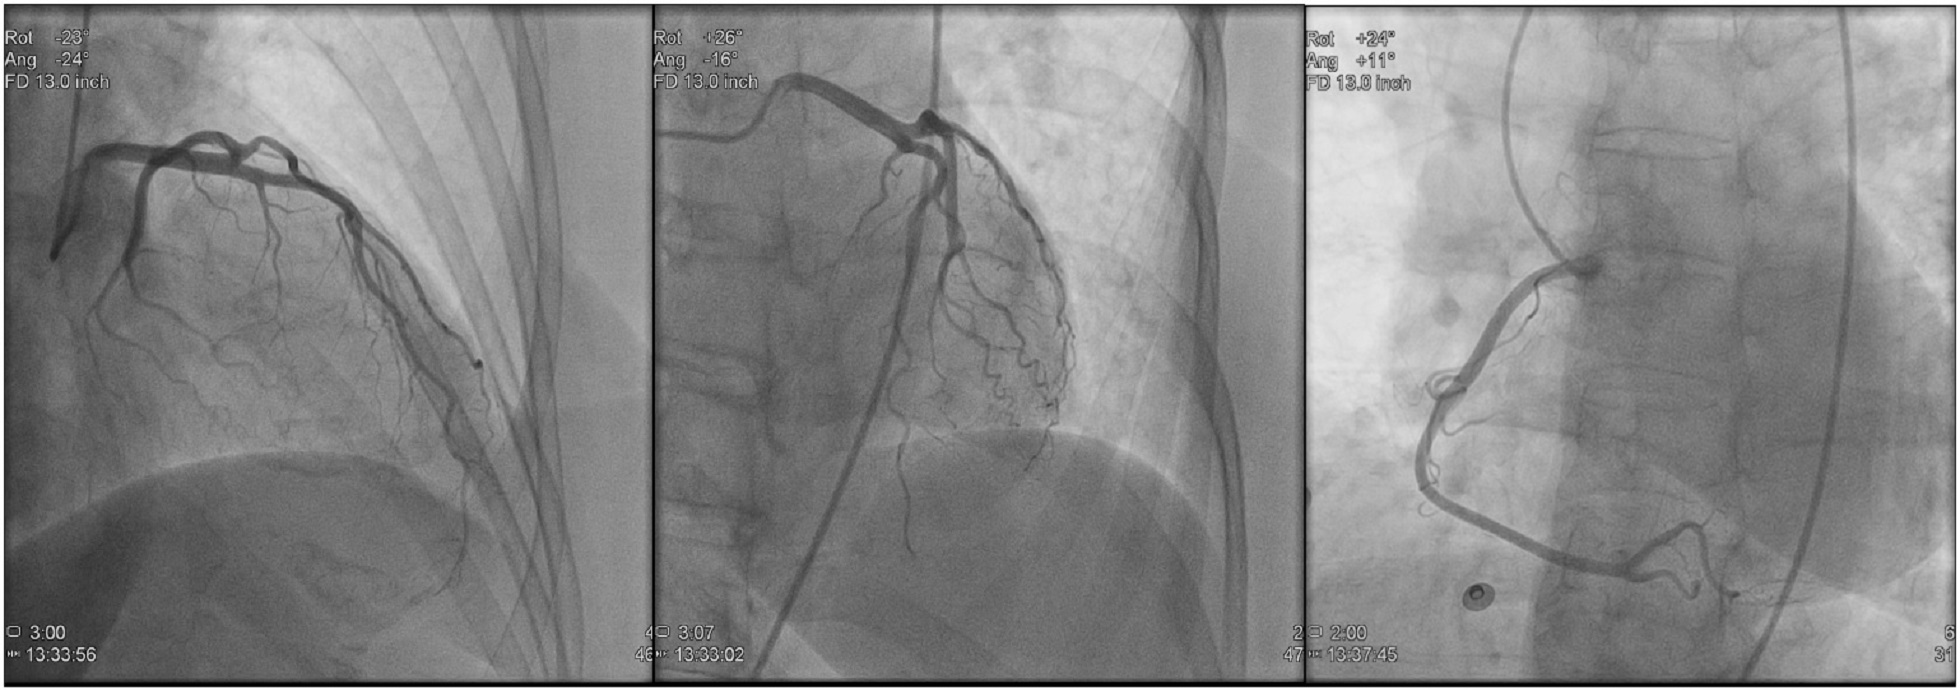

• Images and diagrams of Coronary Arteries